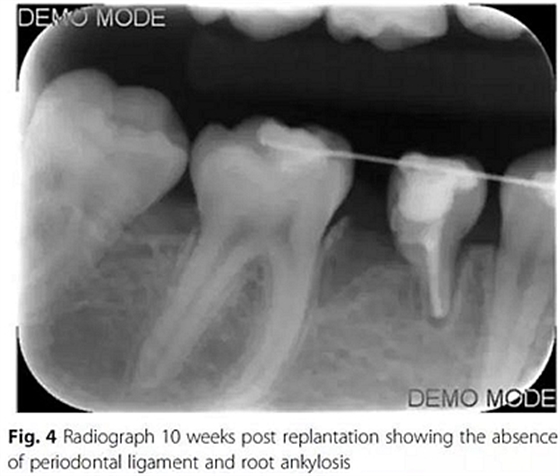

10周后,根據(jù)臨床和影像,形成乳磨牙牙槽粘連,移除牙弓夾板。下一步,在右下第一磨牙上粘接帶環(huán),在第二乳磨牙和下頜第一前磨牙上粘接托槽,在恒磨牙和乳磨牙之間安裝T型曲前移第一恒磨牙。T型曲共激活9次。